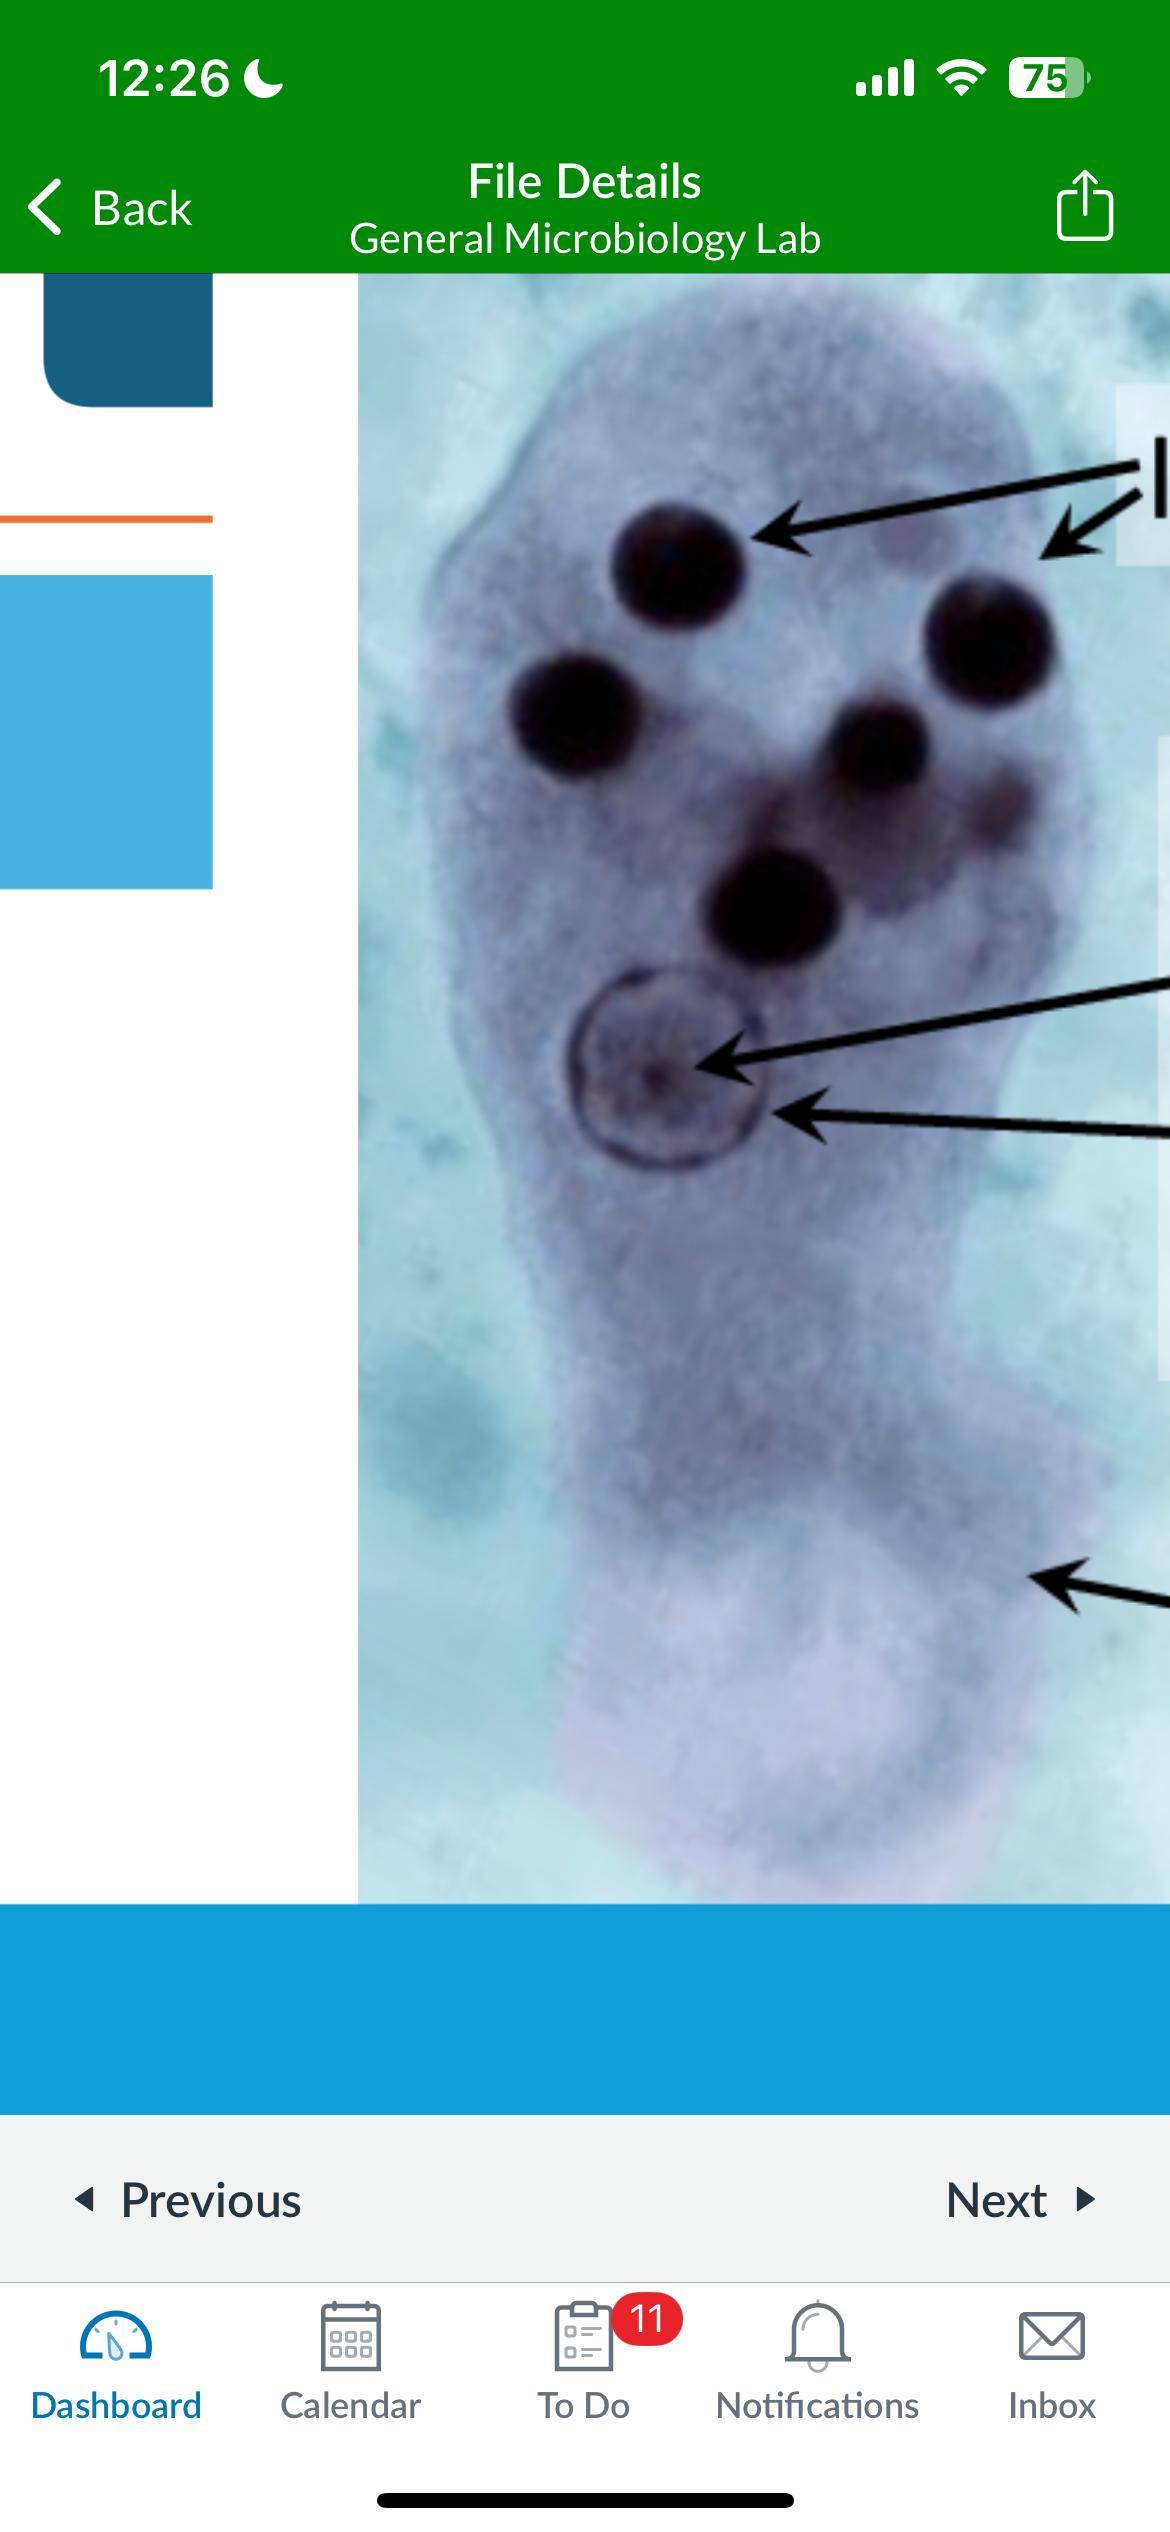

term image

Plasmodium malariae